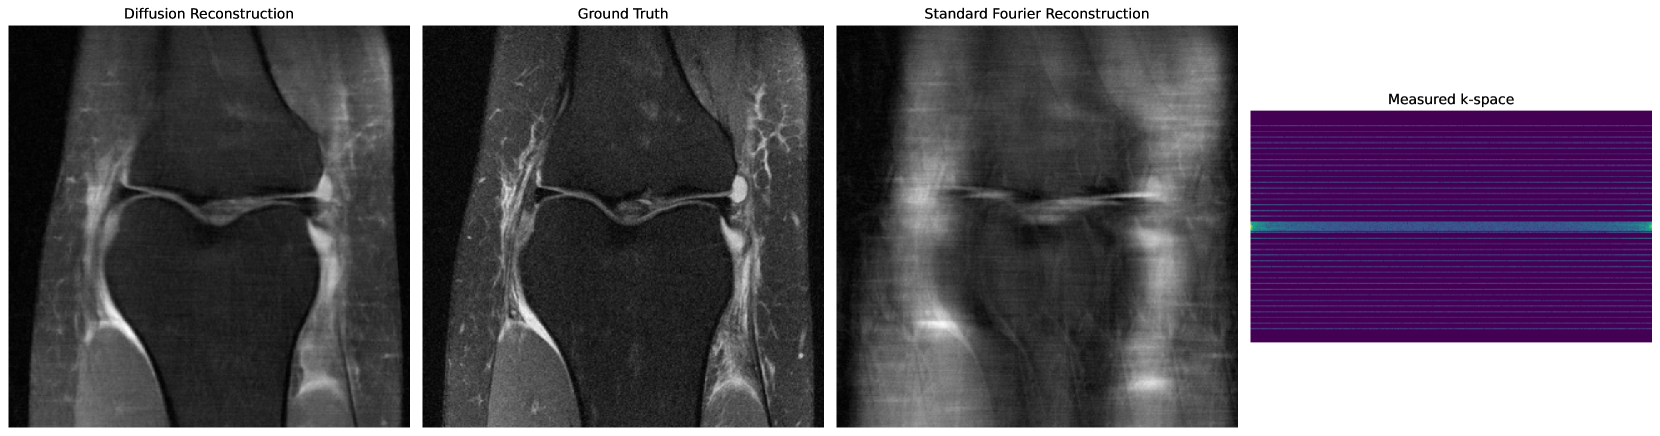

Appendix B Diffusion Active Learning for MRI

MRI operates within the same framework described in Equation (1), with , where is a complex value object, is a forward model consisting of taking the Fourier transform, which produces the k-space of , followed by a masking that takes a single row (or column) specified by the index . The set of possible measurements is then the set of all possible rows of the k-space of . Assuming a Gaussian distribution of the noise , the reconstruction problem can be solved using maximum-likelihood inference given by Equation 2.

Given the similarity between this setup and the CT setup studied in the main body of this paper, we extend our framework to work with MRI reconstructions using the formulation of Diffusion Active Learning and Algorithm 1.

Figure 8(a) summarizes our results for the FastMRI dataset. As generative models, we consider diffusion models, SWAG, and Ensemble; and for acquisition, we consider two non-adaptive allocations , uniform and low to high, explained below, and the active learning allocation based on Equation (3). On each acquisition step, both non-adaptive allocations choose the non-measured row closest to the center from a pool of predefined available rows. For an AL process with steps, the pool of rows for the uniform allocation consists of equispaced rows, while for the low to high allocation, the pool consists of the rows closest to the center, i.e., the ones with the lowest frequencies.

As in the case of CT, the diffusion model outperforms all other generative models in terms of PSNR with up to reduction in the number of sampled rows needed to achieve the same PSNR.

Fig. 16 and Fig. 17 show qualitative results of the reconstructions. Here we can see that the diffusion model obtains a sharper image with as few as 10 adaptively chosen measurements (plus two pre-selected columns), while the other generative models struggle to obtain a meaningful reconstruction.